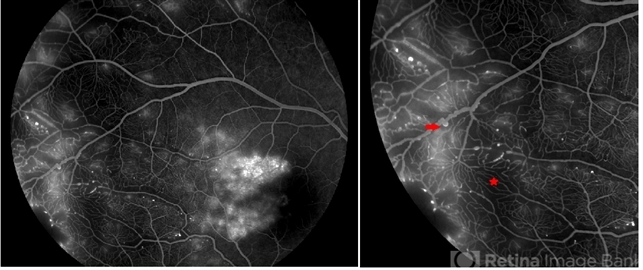

- Fundus florescence picture in AV phase of a 16 year old Indian male. FFA showed both early and leakages with multiple aneurysms (red arrow) over dilated tortuous temporal vessels. Capillary drop out areas (red star) where also seen temporal to the fovea.